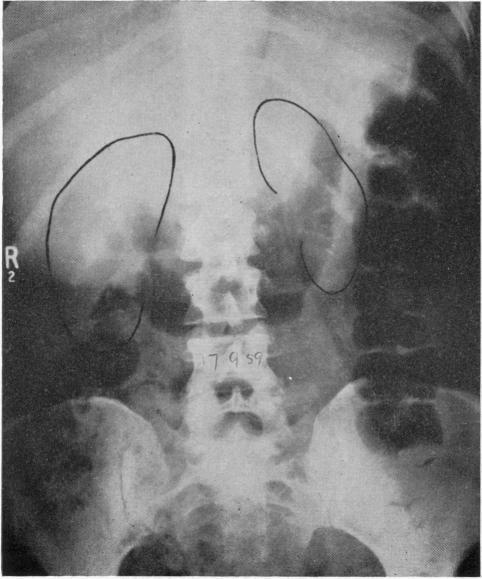

An Unusual Case of Renal Failure and Hypertension.

Br Med J. 1963 Jul 20;2(5350):167-70.